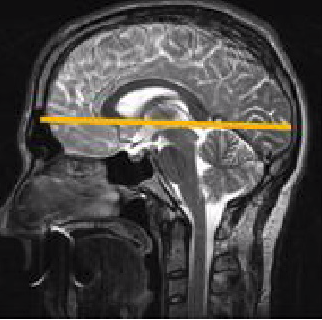

SAG 3D T1 TFE

Be sure to cover the brain both LR and AP. Leave about 15 mm from top of the head to the top of the FOV.